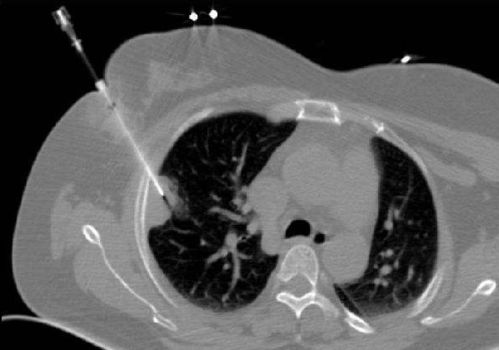

對肺穿刺活檢的目的要明確,不能對疑診血管性病變進行穿刺活檢。對大血管旁病變穿刺活檢要慎重選擇最佳路徑,避免損傷血管。

最主要的并發(fā)癥為肺內(nèi)出血及氣胸,最好在CT引導(dǎo)下進行以提高準確性,由富有操作經(jīng)驗的醫(yī)師來做,可提高成功率及減少并發(fā)癥。手術(shù)中對某些特殊麻醉劑要按使用說明進行(有些要做過敏試驗)。

只是穿刺適用于外周性包塊,離胸壁較近的。最大的副反應(yīng)是氣胸,發(fā)生率較低,且容易處理。